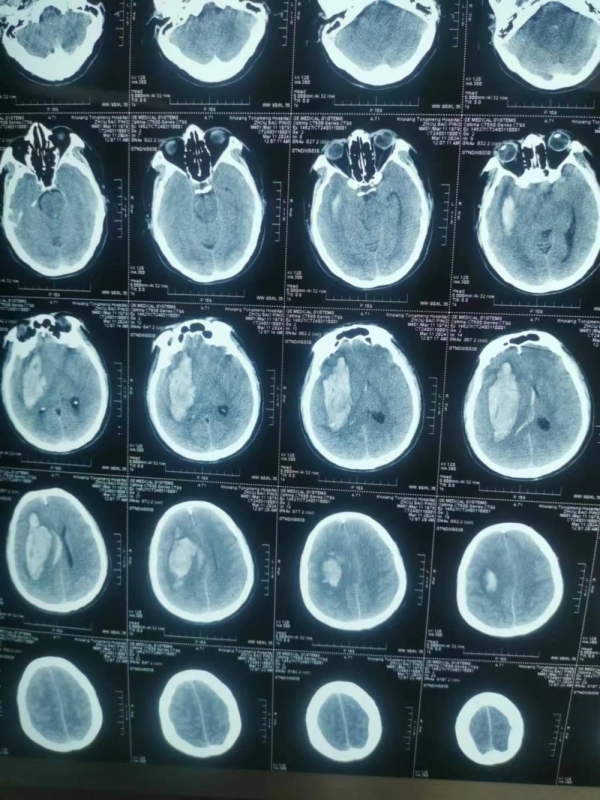

術(shù)后,評估、討論、制定方案·····抱著必須讓患者活下來,盡力達到最佳救治效果的目標(biāo),楊主任團隊積極展開一系列專業(yè)治療,周先生還較年輕,是家里的頂梁柱,家屬期盼很高,但他腦出血量又較大,術(shù)后“腦腫脹”風(fēng)險極高,主管醫(yī)師胡升陽頂著壓力,持續(xù)監(jiān)測顱內(nèi)壓變化,并詳細記錄數(shù)值變化規(guī)律,調(diào)整治療藥物用量;每日見到患者家屬“期盼的眼神”,ICU醫(yī)護人員都身同感受,時刻盡己所能,助力患者病情恢復(fù)。

“功夫不負有心人”,術(shù)后第6天,周先生復(fù)查結(jié)果顱內(nèi)水腫較前明顯好轉(zhuǎn)。但暫時的好轉(zhuǎn)并不意味著患者已經(jīng)“轉(zhuǎn)危為安”,術(shù)后各種并發(fā)癥逐漸出現(xiàn),“肺部感染”,“臟器功能不全”,持續(xù)威脅患者生命,而這其中任何一種并發(fā)癥對患者都有致命的危險。巨大的壓力再次壓到了醫(yī)生們肩上,討論、評估、制定方案、修改、再討論ICU醫(yī)護們?nèi)找岳^夜將救治方案得到最優(yōu)。